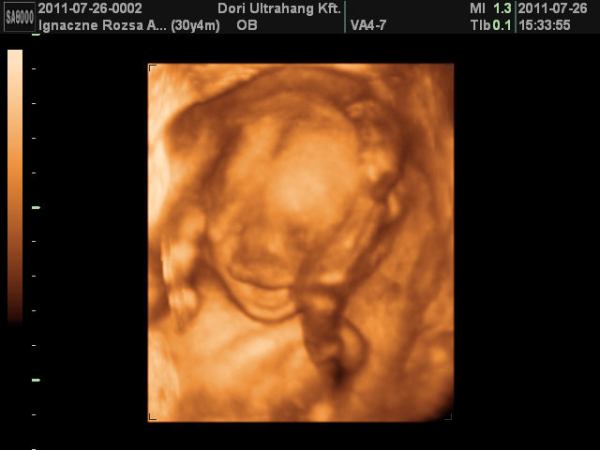

Nálunk minden oks ma voltam dokinál zárt a méhszájam de a méhnyak elég rövid.Jövő 7-en kedden fexek be a kórházba szerdán doki össze varrja a m.szájat, csüti jöhetek haza.Uh-on babám most is szégyenlősködött, de egy pillanatra láttuk a lába közét és nem volt ott semmi lifegő :wink: .Kedden is lesz egy uh, talán ott jobban látjuk a dolgokat.